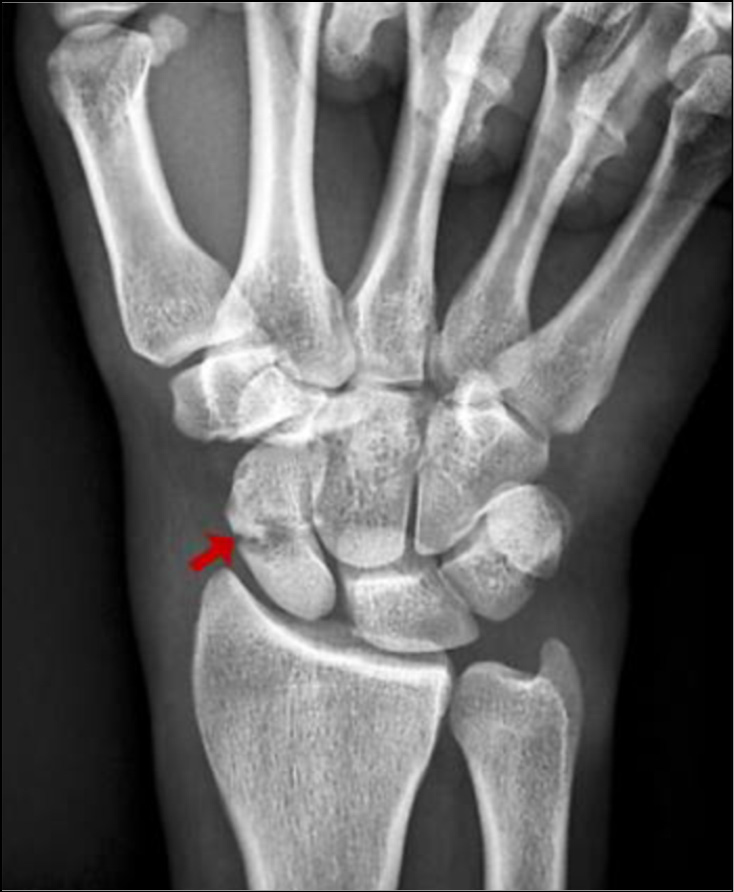

Рис. 2. Рентгенограммы правой кисти в прямой и боковой проекциях. Пациент А., 31 год, падение на плоскость во время ходьбы и бега, диагноз: «Закрытый перелом шейки V пястной кости правой кисти, давность 2 сут» (стрелки).

Группа 2. Изучены характер, течение и исход переломов пястных костей у 218 лиц, получивших травму при разных обстоятельствах, связанных с воздействиями тупых предметов. Как видно из табл. 2, наибольшее количество переломов обусловлено падением пострадавшего на плоскость ― 66,5% (рис. 2); на удары тупым предметом и частями тела человека в область кисти пришлось 11,9 и 9,2% соответственно. Другие обстоятельства травмы составляли от 0,9 до 2,3%.